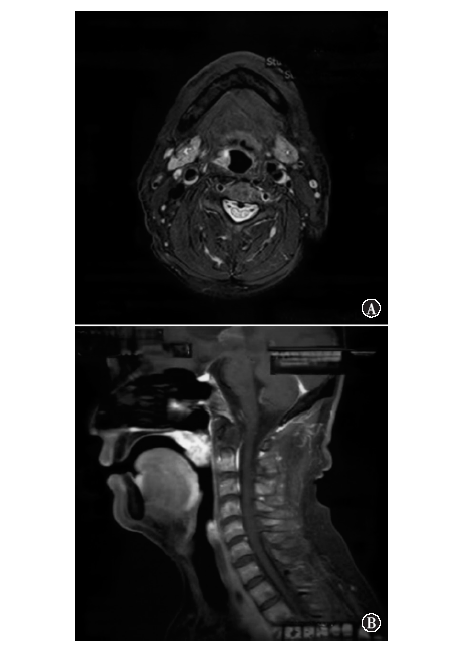

Shindo M, Yoshida Y, Tominaga K, et al. Skin metastasis of hypopharyngeal carcinoma to the nasal tip[J]. Yonago Acta Med, 2013, 56(2): 57-58.

Lopes Alexandre P, Matos R, Marques A, et al. Clown nose: a rare hypopharyngeal cancer metastasis[J]. Ear Nose Throat J, 2022: 1455613211069349. DOI: 10.1177/01455613211069349.

Kocak Z, Uygun K, Uzal MC, et al. Unusual metastatic site in a case of carcinoma of the hypopharynx: nasal tip[J]. J Otolaryngol, 2005, 34(4): 250-252. DOI: 10.2310/7070.2005.34409.